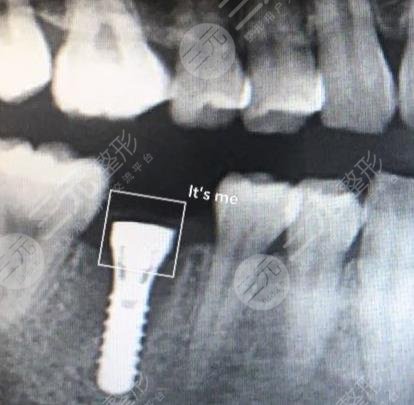

I am a lecturer in the company, usually I may have to face the whole company for training, so the requirements for appearance are relatively high, because not long ago I lost a tooth, resulting in the whole appearance has also been affected, and when I speak, it is also very uncomfortable, so I have always wanted to carry out dental restoration, and later under the introduction of a friend, I found a local well-known dental hospital, in fact, when I was looking for a hospital, I also learned some related methods of repairing teeth, in fact, I am more inclined to dental implants After coming to the hospital, I didn't expect the doctor to recommend dental implant surgery to me.

The price of dental implants may be relatively high, but I know that the results are better, and the maintenance time will be longer, it can be said that it can bring a one-time treatment, before doing dental treatment, the doctor also introduced me to some related knowledge, I know a lot, during the operation injected anesthetic, so I will not feel pain at all, this is not to worry. When I just had dental implant surgery, I may feel some swelling, and there will also be bleeding, I was like this at the time, and the doctor who was still worried at that time told me some relevant details for me to pay special attention to, this situation is normal, generally it will slowly disappear in about 3 to 5 days, and if it is really on the 4th day, my tooth swelling will slowly disappear.

It has been more than two months since I had dental implant surgery, because the time period of dental implant surgery is very long, but according to the good results, the whole tooth is better, and I can chew food normally, just like my own real teeth, I am more grateful to the doctor for the help I have brought to me, of course, I am also glad that I chose this hospital, I have many friends with bad teeth around me I also recommended them to come to this hospital for treatment, I believe that I will be able to get better dental restoration.